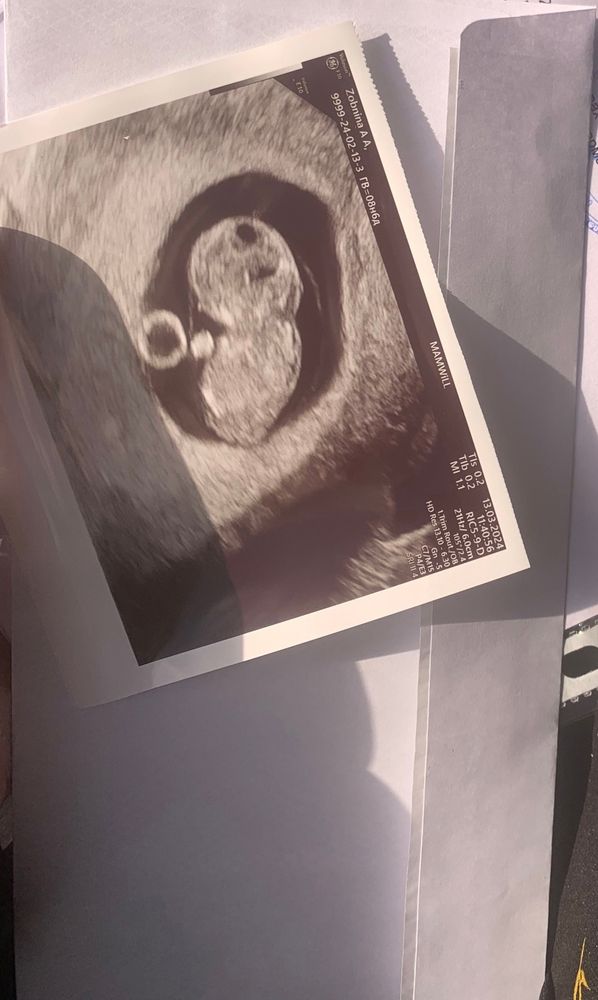

Узи 9 недель

Катерина , ой, я вообще без понятия 😄 Она сказала, что развивается хорошо, отслоек нет. Потом зачем - то навела на воротниковое пространство, сказала про него, но что увеличено не сказала. Сказала мол, что лучше бы пораньше скрининг сделать, на 12-13 неделе, чтобы посмотреть на наличие к ХА, вот так вот) Может я её не так поняла, но мне показалось, что что - то не так по её виду и выражению лица. Врач хорошая, главный врач в этой платной клинике, поэтому и расстроилась как - то. Сейчас у меня уже срок 9.4, а то узи было сделано в 8.6, так и хочется ещё раз на узи сходить до скрининга 😁 Не могу, нервничаю слишком из-за этого

Там же вообще еще крошка какой твп мерить,у меня был такой же карапуз на 9 неделе.В 12+5 по скринингу твп 1,5 и все шикарно.Вам рано разводить панику,дождитесь скрининга 🥰

Рано ещё для данного показателя. Дождитесь скрининга)))все хорошо с вашим мальчонком( по поводу пола чисто мои предложения по данным фото)